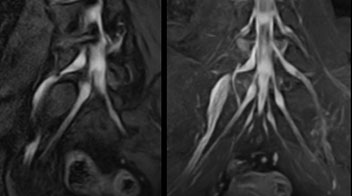

At Northern Fukushima Medical Center in Japan, excellent MRI visualization of nerves helps support confident diagnoses and informs surgical treatment decisions for patients with lower limb symptoms. MRI technologist Tanji and orthopedic surgeon Dr. Yabuki share how direct nerve visualization with the 3D NerveVIEW method adds information when diagnosing atypical herniations. The additional insights changed their way of working and benefit their patient care, as illustrated by some clinical examples.

“In patients with lower extremity neurological symptoms, NerveVIEW helps us to determine the disease matching the patient’s symptoms by directly visualizing the nerves. We use the sequence mainly, when there is suspicion of intraforaminal stenosis, extraforaminal stenosis or lateral disc herniation, which is often based on routine T2- and T1-weighted images. Additionally, the excellent depiction of the course of nerves makes NerveVIEW a good navigator when applying treatment such as block therapy or surgery.”

“In such case, we would then browse through axial T2-weighted MR images slice by slice and mentally reconstruct the actual situation based on both radiculography and MRI. Fortunately, NerveVIEW can now very well show nerve courses and presence of nerve compression or edema in one single image series.” “We have often seen NerveVIEW directly depict details of the nerve compression that were not observed by radiculography. Therefore, we think that with NerveVIEW we can reduce the number of invasive examinations, especially for some patients with lumbar plexus symptoms.”

“Before NerveVIEW, diagnosis by MRI alone was sometimes difficult, unless there was a strong suspicion based on clinical symptoms,” says Shoji Yabuki, MD, DMSc, Orthopedic surgeon at Fukushima Medical University School of Medicine. “This is why we routinely perform selective lumbosacral radiculography (nerve root block) and x-ray in such cases. However, radiculography can only depict nerves as far as the contrast agent reaches. When a nerve is distorted by compression, the contrast agent will not pass through this compressed area, preventing us from evaluating the full nerve compression.”

The key concept in MR neurography, Dr. Yabuki stresses, is the ability to directly visualize spinal nerves, versus inferring the presence of pathology indirectly. “Before NerveVIEW, we estimated compression of the nerve by looking for the presence or absence of fat signal on other MR images,” he says.

“For example, in sagittal images, when the presence of fat is observed in the intervertebral foramen, it suggests that there is a margin around the nerve. Similarly, the absence of fat indicates that the nerve is being compressed. So, we used to deduce nerve compression indirectly. With NerveVIEW, however, we can observe the condition of the nerves directly, regardless of the presence or absence of fat. We always prefer such direct observation of anatomy over having to make an inference about it.”

“Although symptoms of typical disc herniation and atypical hernia are very similar, the actual site of herniation is different. It is therefore important to characterize the nerve’s condition both inside and outside of the intervertebral foramina. “Conversely, if we see no abnormality in NerveVIEW, we can assume at least that there is no severe condition that requires surgery. Like this, it can help us avoid unnecessary surgery. NerveVIEW can have a tremendous impact in this way.”

“NerveVIEW is really useful for those cases where a nerve disorder is strongly suspected based on the clinical examination but our regular MRI images do not show any findings. These atypical herniations and spinal canal stenosis, occurring in 5% to 15% of the total lumbar herniation/stenosis cases are our main target when using NerveVIEW,” says Dr. Yabuki.